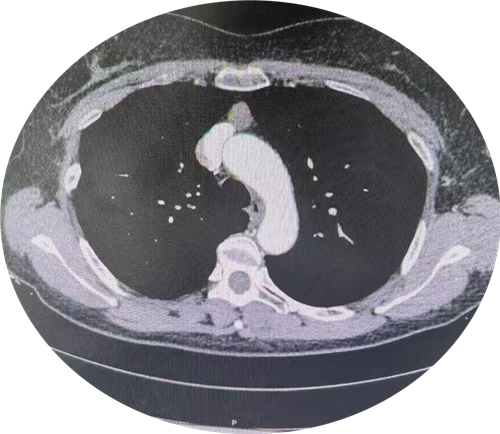

为攻克何女士前纵隔肿瘤这一难题,胸外血管外科医生组迅速展开多轮病例讨论。最终,他们选定了极具创新性的剑突下纵隔肿瘤切除术。这一术式以胸骨最下端的剑突为突破口,如同开辟了一条精准的“生命通道”,既能直抵病灶,又巧妙避开传统手术对胸廓骨骼、肌肉的大面积损伤,实现创伤小、视野清、术后疤痕隐蔽的多重优势,堪称温柔与硬核并存的医疗智慧。